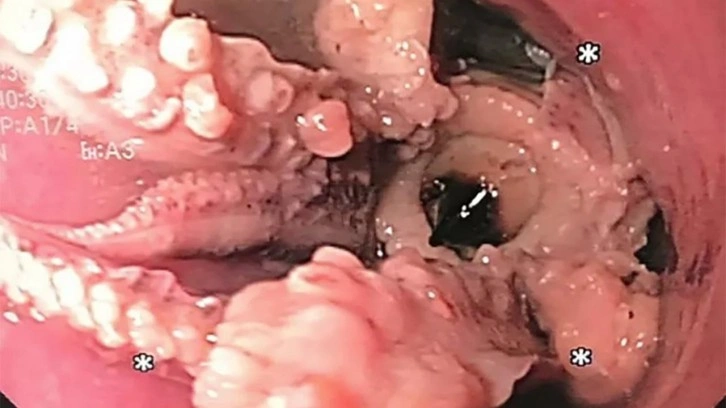

Singapur’da ismini açıklamak istemeyen bir adam akşam yemeği yedikten sonra sürekli kusma ve boğaz ağrısı şikayetiyle hastaneye başvurdu. Doktorlar yaptıkları tarama sonucunda 55 yaşındaki hastanın yemek borusunda yoğun bir kitlenin olduğunu ortaya çıkarttılar.